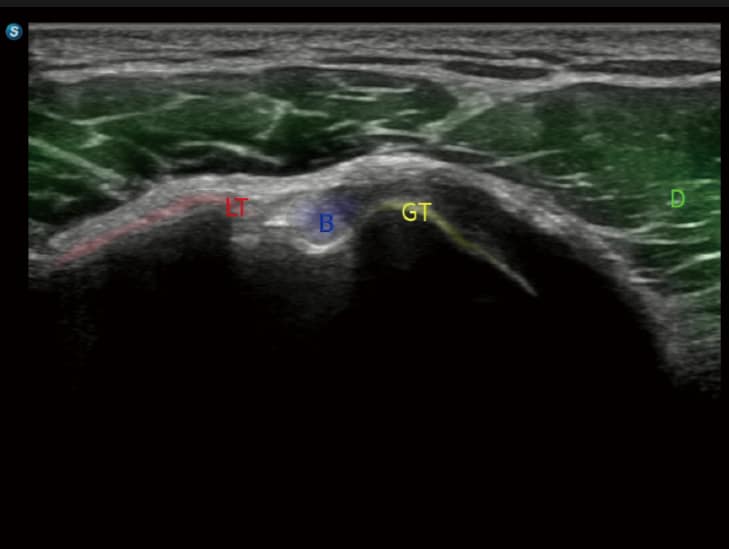

• S-Thyroid & T-MSK: Automatisierte Erkennung und Klassifizierung von Schilddrüsenläsionen nach ACR-TI-RADS sowie die Identifikation standardisierter Gelenkebenen im Bewegungsapparat.